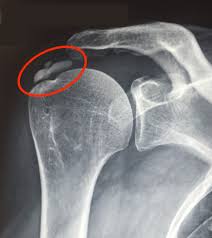

O diagnóstico é realizado por meio de exames clínicos e imagens, como a radiografia, ultrassonografia ou a ressonância magnética, por exemplo. Dessa maneira, estes exames ajudam a visualizar os depósitos de cálcio nos tendões e a avaliar a gravidade da inflamação.